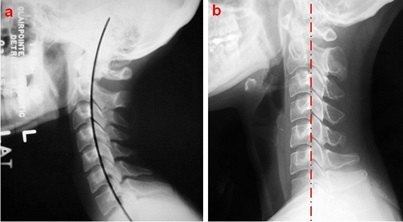

Sep 23, · 颈椎压迫神经可以表现为头晕、头痛;甚至偏头痛、恶心,心前区不适,此为交感神经性颈椎病的常见症状。 因此一方面应避免长时间的低头活动,可以佩戴颈托保护、颈部外用膏药,配合局部物理治疗,如热敷、烤电、针灸都可以在一定程度上改善。 除此以外,可以适当的考虑颈椎牵引治疗,对神经受压所表现的症状也有一定程度的改善。 如果经过以上治疗仍然无Nov 26, · 腰椎间盘突出压迫神经,这说明突出部已经比较大。如果保守治疗两个月,包括牵引、理疗、针灸、外敷膏药等方式,效果不好,建议采取手术治疗。手术治疗包括介入、微创或者开放手Sep 05, 18 · 您好,颈椎病症状主要是由于神经受压引起的,那么治疗关键就在于解除对神经的压迫。 开刀手术是其中的一种的方法。 但是该病属于退行性疾病,一般情况下建议先配合保守治疗。

1 问: 颈椎压迫神经一定要手术吗 答: 不一定需要手术。中医的针灸、推拿、整脊加上自身锻炼(如练以宗第1到第7式)和服用中药。可以恢复。Apr 06, 16 · 开刀手术主要是针对颈椎病病情严重的患者或者保守、微创治疗无效的患者,往往作为最后的选择。 开刀手术存在创伤大、流血多、误伤其他组织等危险,也能导致术后脊椎不稳,易复发,影响患者以后的工作和生活。 相对而言,开刀手术的治疗费用几千到几May 30, 16 · 颈椎病症状主要是由于神经受压引起的,那么治疗关键就在于解除对神经的压迫。 开刀手术是其中的一种的方法但是该病属于退行性疾病,一般情况下建议先配合保守治疗。 对于正规保守治疗三个月以上,症状一点都没有缓解,严重影响生活和工作的情况下,结合查体考虑手术来治疗。 目前大多数患者选择药物方法来治疗,口服药物、打针、输液等方法,但是只能缓解

Nov 28, 14 · 颈椎病压迫脑神经症状大家一起跟随小编来看看吧 病例一: 病情描述 颈椎压迫脑神经有什么症状?血压正常。突然左半边头疼头晕右边胳膊和腿不好使,一会就好。做ct说没有事是否是颈椎压迫脑神经有什么症状?怎么治疗?谢谢 问题回答Sep 26, 18 · 如果是颈椎的骨折合并神经的压迫,一般需要开刀手术。 手术暴露到骨折的地方,彻底去除骨块对神经的压迫。 手术以后可以配合营养神经的药物比如甲钴胺,有助于神经功能的恢复。Aug 19, · 颈椎病需要手术治疗吗? 颈椎病似乎是困扰每一个职场人士的问题。得了颈椎病怎么治?需不需要手术治疗?南方医科大学南方医院副主任医师郑帅表示,颈椎病的治疗方法主要分为保守治疗和手术治疗,85%以上的颈椎病患者均可以通过保守治疗取得良好效果。